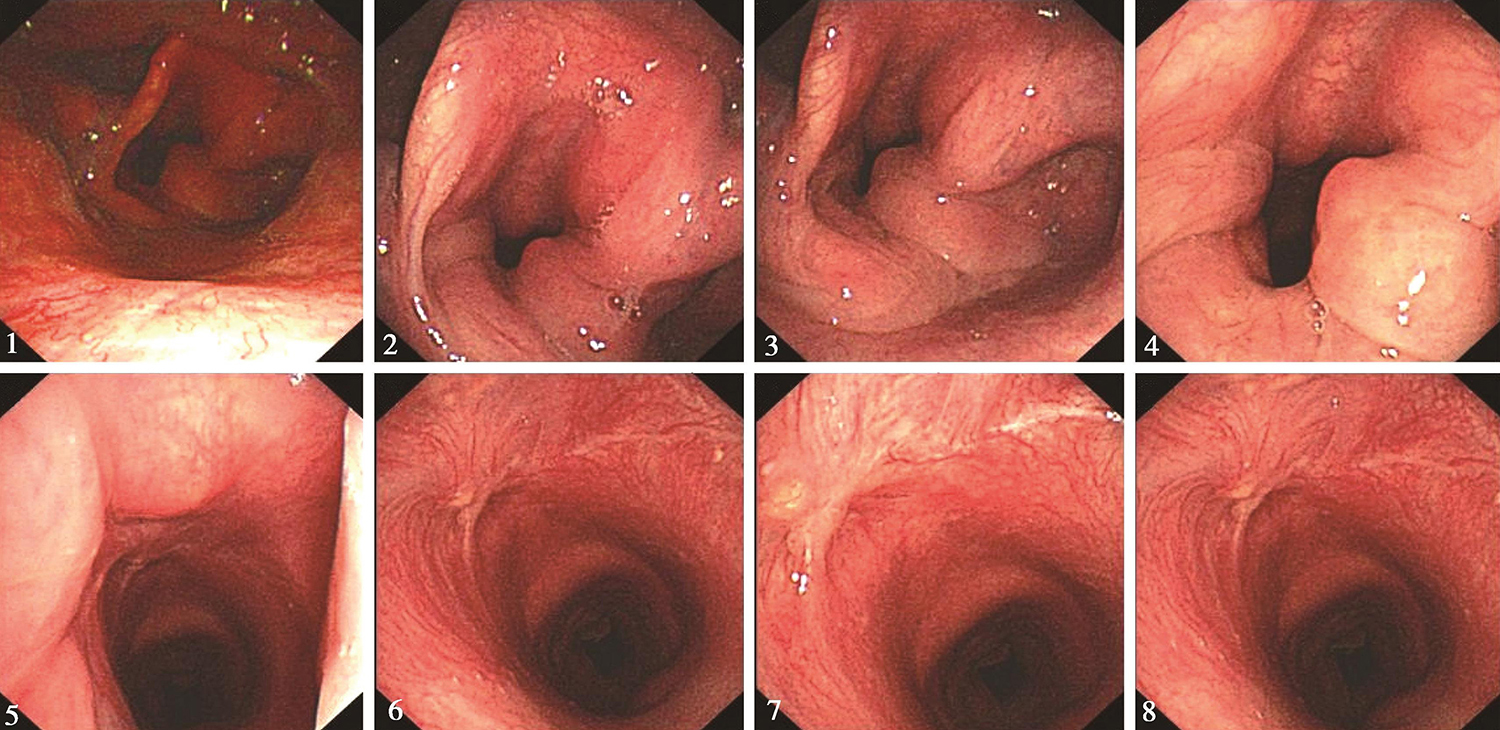

1小时条评论内镜黏膜下剥离术(endoscopic submucosal dissection,ESD)是以内镜黏膜切除术(endoscopic mucosal resection,EMR)为基础,通过在黏膜下注射含有染色剂的生理盐水,利用几种特殊的高频电刀将病灶周围黏膜切开,再将病灶完整剥离,达到治愈目的的技术。内镜下黏...